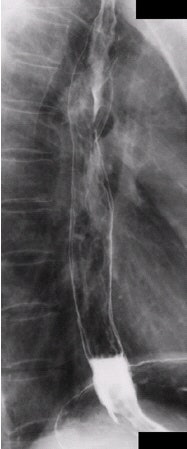

![]() |

| Left anterior oblique projection, single-contrast esophagram. Image courtesy of Dr. Naveed Ahmad. |